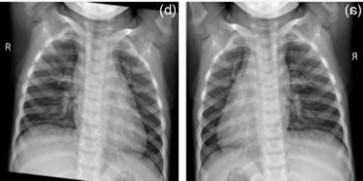

Table 2 shows the chest X-rays from three categories: pneumonia, tuberculosis and normal chest X-rays. The pneumonia image highlights red circles to indicate where the infection has occurred in the lungs. The image of tuberculosis reveals the usual signs, including abnormal conditions in the lungs. On a normal chest X-ray, the lungs are healthy and show no signs of abnormality. Many DL models in medical diagnostics were trained with these images.

Pneumonia Image | Tuberculosis Image | Normal Chest X-ray |

![]() | ![]() | ![]() |